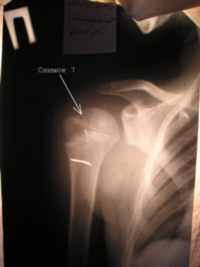

Снимок 6 (21.08.04) – полное анатомическое и структурное восстановление проксимального отдела правой плечевой кости в сравнении с левым плечевым суставом (Снимок 7).